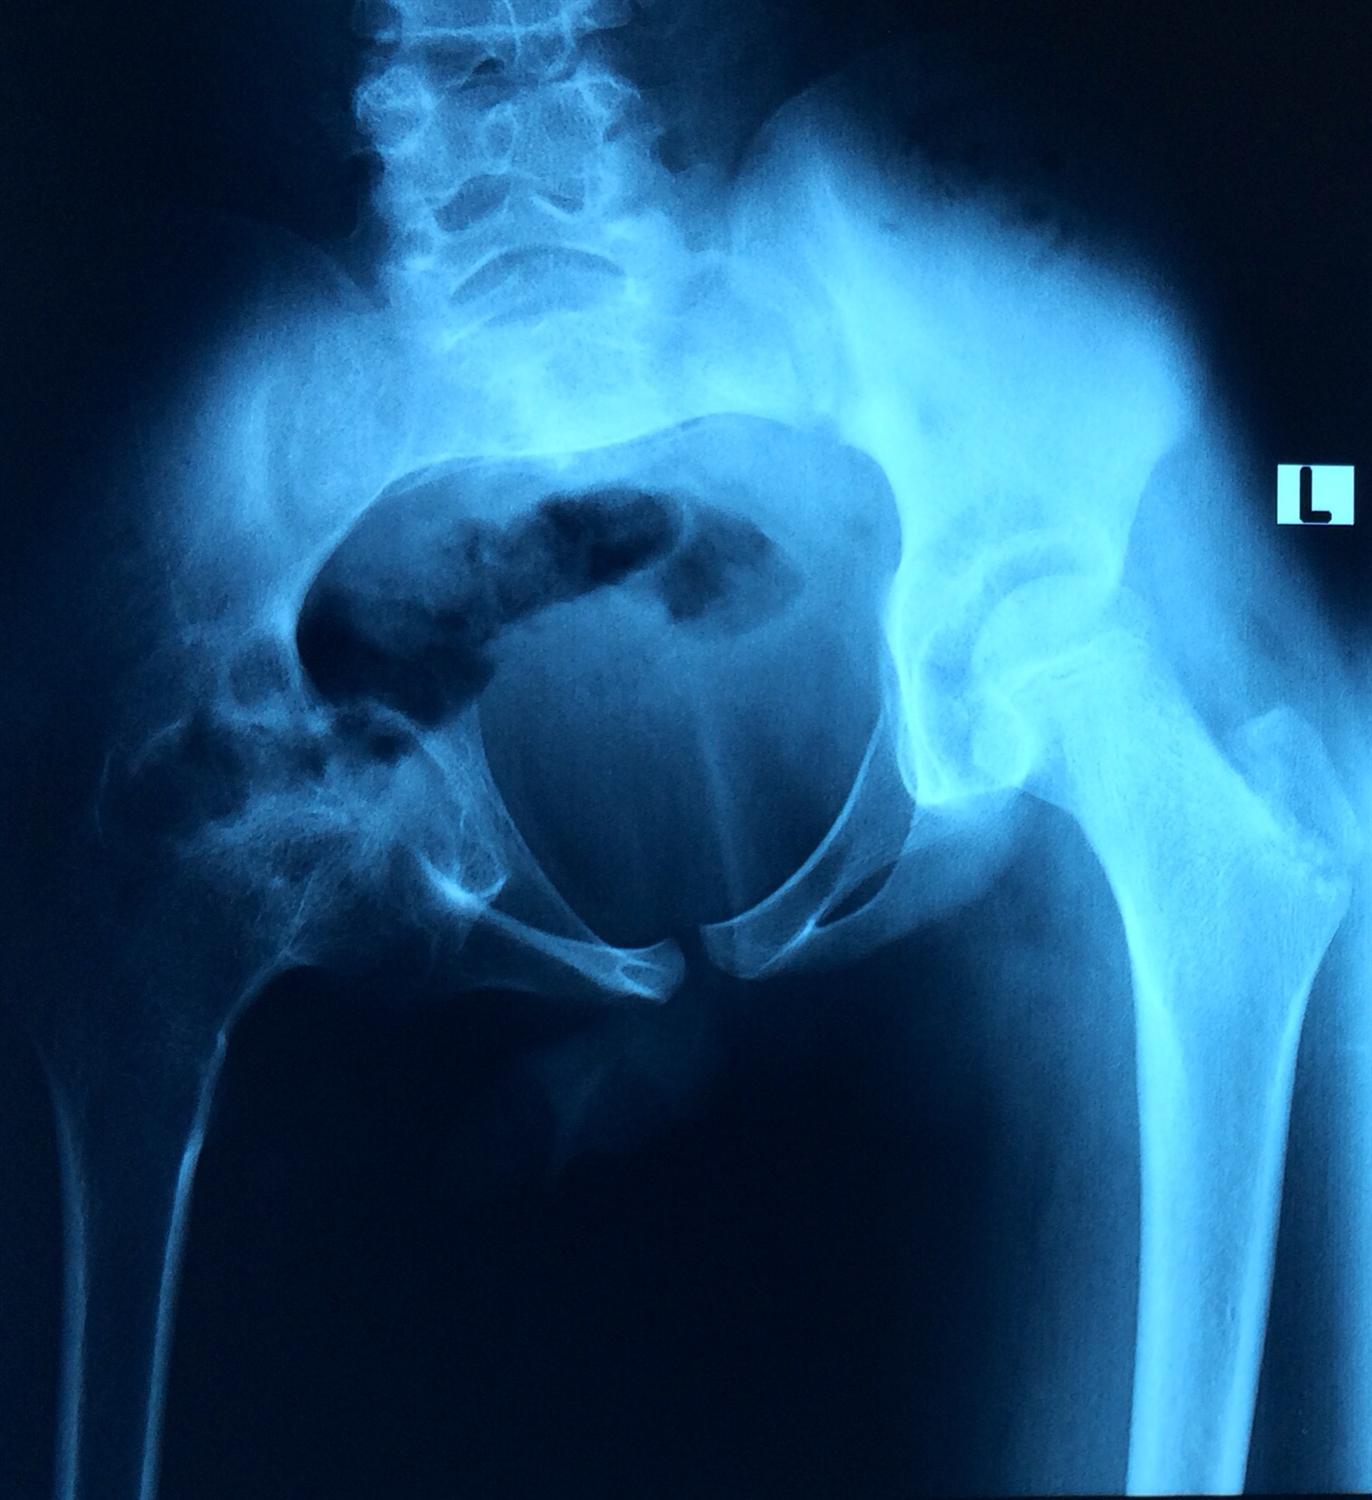

Arm Compartment Syndrome Orthobullets . Acute compartment syndrome (acs) is a surgical emergency. There have been multiple causes of upper arm compartment syndrome. Compartment syndrome is a surgical emergency. Compartment syndrome is a condition in which increased tissue pressure within a limited space compromises the. An upper arm compartment is a rare type of compartment syndrome. A table outlining the emergency evaluation and management of acs. Failure to diagnose it and delays in decompressing the involved compartment(s). Hand & forearm compartment syndrome are devastating upper extremity conditions where the osseofascial.

Hand & forearm compartment syndrome are devastating upper extremity conditions where the osseofascial. Compartment syndrome is a condition in which increased tissue pressure within a limited space compromises the. A table outlining the emergency evaluation and management of acs. There have been multiple causes of upper arm compartment syndrome. Failure to diagnose it and delays in decompressing the involved compartment(s). Compartment syndrome is a surgical emergency. An upper arm compartment is a rare type of compartment syndrome. Acute compartment syndrome (acs) is a surgical emergency.

Arm Compartment Syndrome Orthobullets Compartment syndrome is a surgical emergency. An upper arm compartment is a rare type of compartment syndrome. Compartment syndrome is a surgical emergency. Hand & forearm compartment syndrome are devastating upper extremity conditions where the osseofascial. Acute compartment syndrome (acs) is a surgical emergency. A table outlining the emergency evaluation and management of acs. Compartment syndrome is a condition in which increased tissue pressure within a limited space compromises the. There have been multiple causes of upper arm compartment syndrome. Failure to diagnose it and delays in decompressing the involved compartment(s).